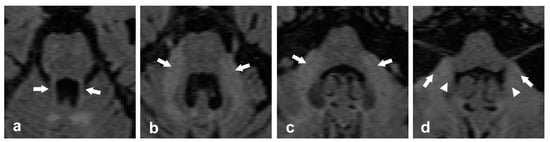

- MRI T2/FLAIR sequences: T2/FLAIR hyperintensities allow the visual assessment of macrostructural damage of the CPs. Hyperintensity, when present, indicates abnormality and may reflect demyelination, Wallerian degeneration, cytotoxic edema, vasogenic edema, etc. [78].

- Basic MRI DWI/ADC sequences: These sequences provide information about the water diffusion properties, aiding in characterization of the evolutionary phase of ischemic lesions and supporting differential diagnosis of space-occupying lesions [79].

- Diffusion MRI and tractography: Diffusion MRI is a relatively new MRI technique that allows for the study of white matter microarchitecture. Tractography is a 3D visualization technique to reconstruct white matter fiber tracts using data collected by diffusion MRI. It enables the visualization of cerebellar tract directionality and decussation and allows the calculation of FA, a key metric that quantifies the directional coherence of water diffusion within a voxel. FA ranges from 0 (isotropic, random diffusion) to 1 (anisotropic, organized tracts). However, FA does not solely reflect integrity—crossing fibers in a voxel can lower FA despite intact tracts, while high FA might reflect loss of one fiber tract, not improved health. Complementary DTI metrics help refine interpretation [80]. A high angular diffusion data acquisition scheme, such as High Angular Resolution Diffusion Imaging (HARDI), together with multicompartment orientation reconstruction methods, such as the multi-shell multi-tissue spherical deconvolution method [81], can resolve multiple intravoxel fiber orientations and are particularly useful in regions with crossing fibers, where traditional diffusion tensor models (assuming a single fiber population per voxel) fall short in capturing the underlying macrostructural tissue complexity [82,83,84].

- MR Spectroscopy: This technique analyzes brain metabolites, providing insight into neuronal integrity and cellular composition. The N-acetylaspartate/Creatine (NAA/Cr) ratio reflects neuronal health, with reductions indicating neurodegeneration, while the Choline/Creatine (Ch/Cr) ratio represents membrane turnover, aiding in the assessment of demyelination and tumor characterization [85].

- Peduncular width: Some studies have reported average values in healthy population measured in T1-weighted sequences. For individuals with a median age of 60.75, with standard deviation (SD) of 9.95 (n = 61), or older (n = 48), the SCP should be measured in the coronal plane, with normal values of 5.09 ± 0.82 mm (SD) or in the axial plane at the level of the inferior colliculus (2.2 ± 0.46 mm). The MCP should be measured in parasagittal slices (9.61 ± 1.1 mm) or in the axial plane at the level of the trigeminal nerve (13 ± 1.8 mm). The ICP should be measured in the axial plane at the level of the connection between the cerebellum and the medulla (5 ± 0.12 mm) [8,86].